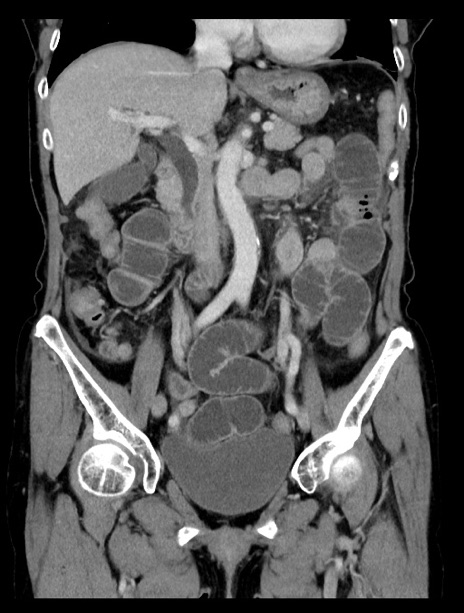

症例23(冠状断像)

【症例】70歳代女性

【主訴】下腹部痛・嘔吐

【現病歴】2日前より腹痛あり。昨日嘔吐あり。症状改善しないため来院。

【既往歴】胃GISTに対して胃部分切除後。

【身体所見】BT 37.1℃、BP 128/77mmHg、腹部:平坦・軟、下腹部に圧痛あり。

【データ】WBC 10200、CRP 0.31